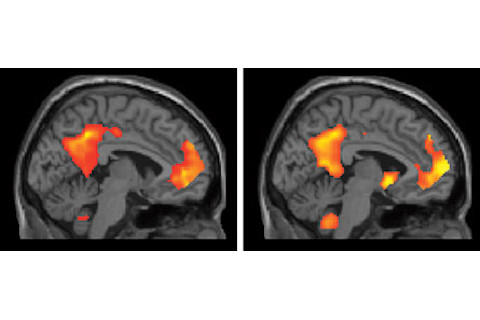

That's what Daniel Schacter at Harvard and his friends have discovered, by doing functional MRI studies of brains subjected to different kinds of cues. (Science Newsreport, Naturereview article, Charlie Rose interview.) Subjects are inserted gently into the giant magnetic field, then asked to either conjure up a memory or imagine a future scenario about some particular cue-word. What you see is that the same sites in the brain light up in both cases. The brain on the left in this image is remembering the past -- on the right, it's concocting an imaginary scenario about the future.